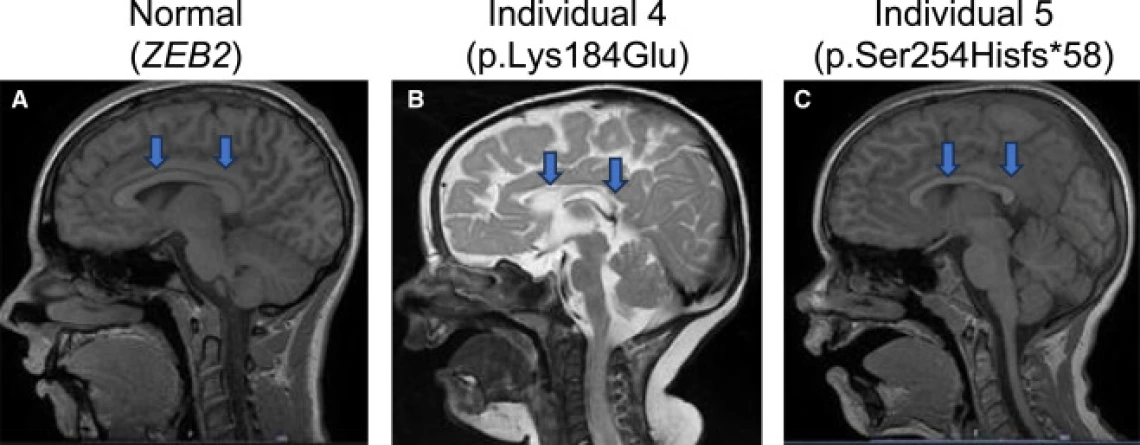

The team’s findings were recently published in The American Journal of Human Genetics in collaboration with researchers from the U.S., Europe, and beyond. The paper identifies mutations in TMEM184B as the cause of a new neurodevelopmental condition marked by developmental delay, seizures, and changes in brain structure.

Her lab, along with collaborators at Lurie Children's Hospital at Northwestern University, turned to model organisms for answers. By removing or replacing the gene in fruit flies and zebrafish, they showed that disruption of TMEM184B causes the same types of neural defects seen in patients – smaller brains, altered neuron growth, and seizure-like activity.

Her team’s analysis found TMEM184B mutations after how cells handle amino acids and other metabolic pathways that fuel brain growth. She said that connection between metabolism and neurodevelopment could change how scientists think about early brain disorders.